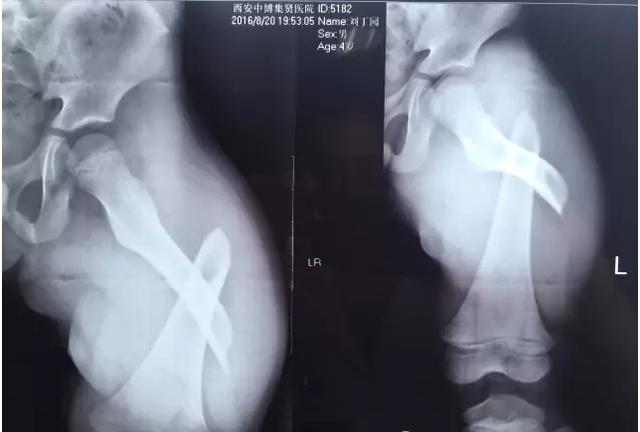

专家表示,大部分骨折是跌倒引起的,最多见的就是骨质疏松性骨折,主要包括桡骨远端、肱骨近端、胸腰椎骨折和髋部骨折。

“许多人跌倒后的第一反应是手撑地,导致摔倒的力量经手腕传导至前臂,从而形成桡骨远端骨折。”北京积水潭二人麻将 新街口院区创伤骨科副主任医师王陶说,如果是髋部骨折,对高龄老人而言,风险和危害更大。

老年人发生骨折后该如何治疗?“对于一些高龄老人,骨折后可能并不适合做手术、打石膏,特别是需要卧床的,保守治疗期间要注意定期翻身、加强营养和适当康复训练,避免出现褥疮、肺炎、下肢静脉血栓等。”上海市老年医学中心骨科主任医师林红说。